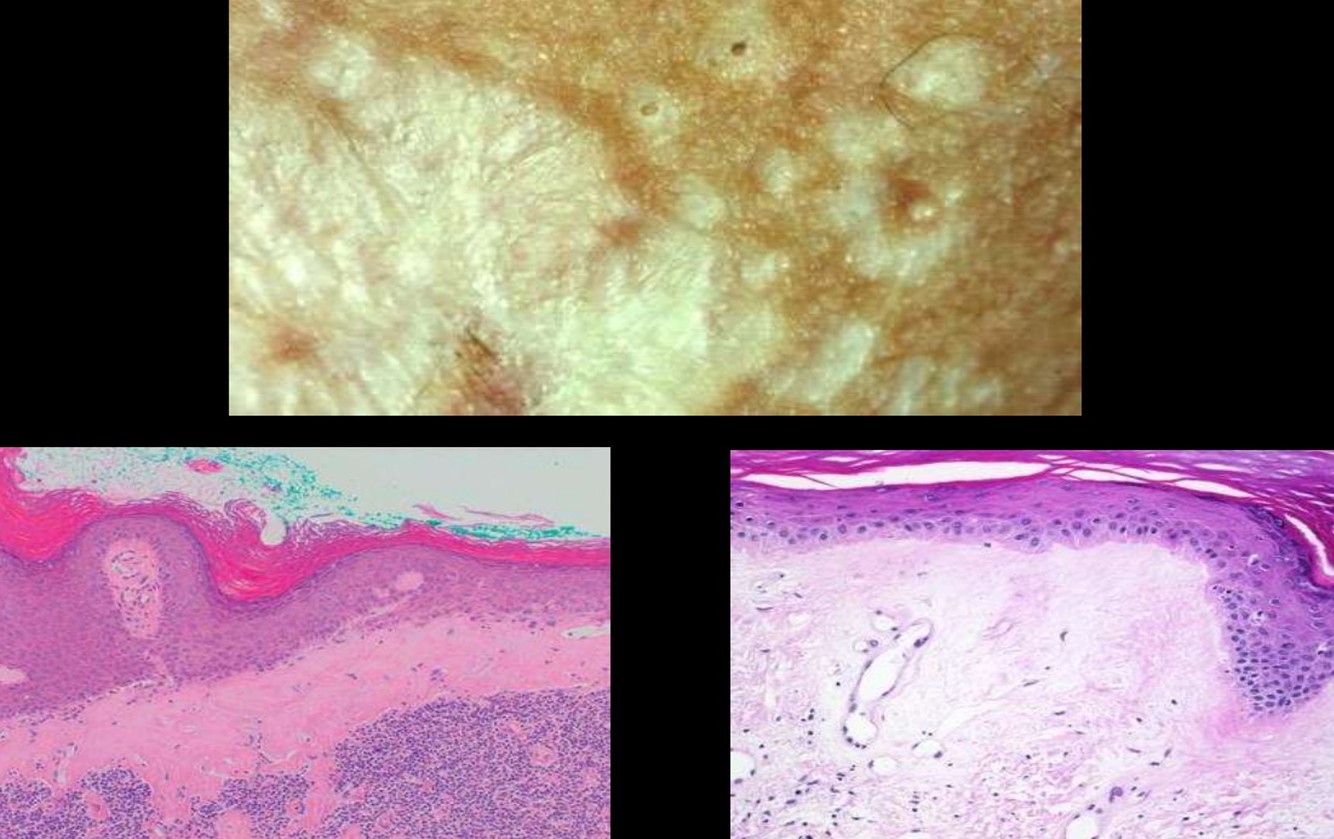

LICHEN SCLEROSUS

• Aka Lichen sclerosus et atrophicus

• 30% of vulvar non-neoplastic lesions

• 90% multiple

• Etiology unknown (autoimmune, hormonal)

• Pruritic irregular white patches

• Subepithelial homogenized zone

• Band of lymphocytes

• Not premalignant – predisposing factor

SQUAMOUS HYPERPLASIA

• aka Hyperplastic dystrophy without atypia

LICHEN SIMPLEX CHRONICUS

• Squamous hyperplasia associated with inflammation

• End stage of many inflammatory skin diseases